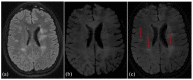

Background: Myelin oligodendrocyte glycoprotein (MOG) antibody-associated disease (MOGAD) and pediatric-onset multiple sclerosis (POMS) share clinical and magnetic resonance imaging (MRI) features but differ in prognosis and management. Early POMS diagnosis is essential to avoid disability accumulation. Central vein sign (CVS), paramagnetic rim lesions (PRLs), and central core lesions (CCLs) are susceptibility-based imaging (SbI)-related signs understudied in pediatric populations that may help discerning POMS from MOGAD.

Methods: T2-FLAIR and SbI (three-dimensional echoplanar imaging (3D-EPI)/susceptibility-weighted imaging (SWI) or similar) were acquired on 1.5T/3T scanners. Two readers assessed CVS-positive rate (%CVS+), and their average score was used to build a receiver operator curve (ROC) assessing the ability to discriminate disease type. PRLs and CCLs were identified using a consensual approach.

Results: The %CVS+ distinguished 26 POMS cases (mean age 13.7 years, 63% females, median EDSS 1.5) from 14 MOGAD cases (10.8 years, 35% females, EDSS 1.0) with ROC = 1, p < 0.0001, (cutoff 41%). PRLs were only detectable in POMS participants (mean 2.1±2.3, range 1-10), discriminating the two conditions with a sensitivity of 69% and a specificity of 100%. CCLs were more sensitive (81%) but less specific (71.43%).